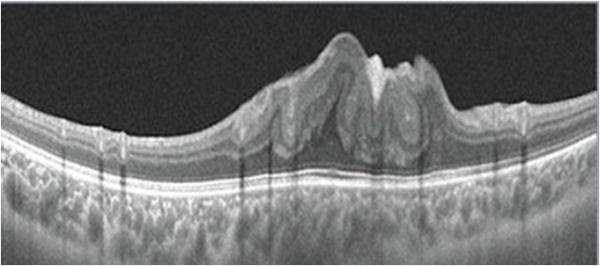

Central Serous Chorioretinopathy (CSCR)

CSCR on OCT shows neurosensory detachment along with clear subretinal fluid often associated with focal serous PED. More recently, enhanced-depth imaging SD-OCT has shown increased subfoveal choroidal thickness in some patients with CSCR, as compared to normal eyes.[25] The outer retinal dipping sign may be noted. Typically, the RPE not involved in serous PED appears straight, unlike inflammatory pathologies, including VKH disease, where the RPE may be undulated.[26]